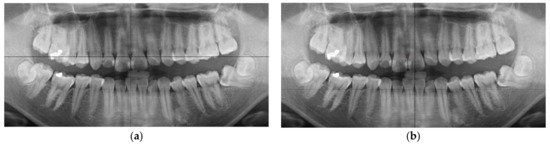

3. Results